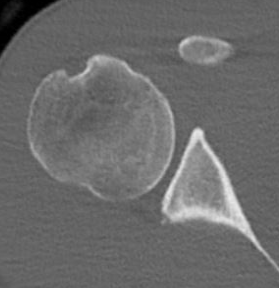

CT

Hill Sachs lesion / posterior bony bankart / glenoid retroversion

Reverse Hill Sachs / Posterior bony Bankart / Glenoid retroversion

Critical posterior glenoid bone loss

- compared successful posterior labral surgery with unsuccessful

- 11% glenoid bone loss - 10 x failure rate

- 15% glenoid bone loss - 25 x failure rate

Glenoid Osteotomy

Posterior instability with retroversion > 10 degrees / glenoid dysplasia